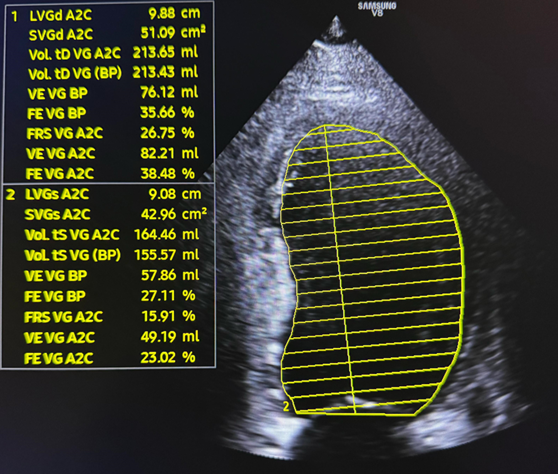

Figure 1: Echocardiography showed reduced LVEF

Figure 2: Echocardiography showed reduced LVEF